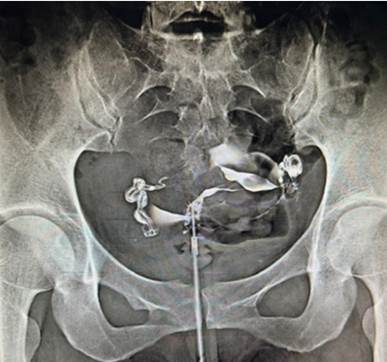

Asiste a primera consulta de fertilidad en centro privado con 36 años, infertilidad primaria 3 años, con buena reserva ovárica. Tenía una HSG de 2 años atrás, con informe reportado como normal, Cotte bilateral positivo; los espermatogramas eran normales, motivo por los cuales la manejaron con varios ciclos de relaciones dirigidas e inseminaciones, todas negativas. Se reevaluaron minuciosamente las imágenes de esta HSG donde fue evidente la rigidez durante el estudio y la distribución irregular del contraste en cavidad, no reportadas previamente, que proporcionan la sospecha de patología tuboperitoneal (Figura 2). Se solicitaron estudios de descarte de TBC a la paciente y a su pareja, que los realizaron en el Hospital Victorino Santaella, en los Teques, con Mantoux/Ziehl Neelsen ambos, positivos. A continuación, se realizó el tratamiento de ambos miembros de la pareja para TBC con triple terapia.

Figura 2 imagen de la primera histerosalpingografía de la paciente del caso 2: de manera discreta existe rigidez de las trompas, persistentes en su posición, ligeras formas arrosariadas, especialmente trompa izquierda, con Cotte bilateral positivo como signo confusor del estudio, todo sugestivo de posible factor tuboperitoneal.